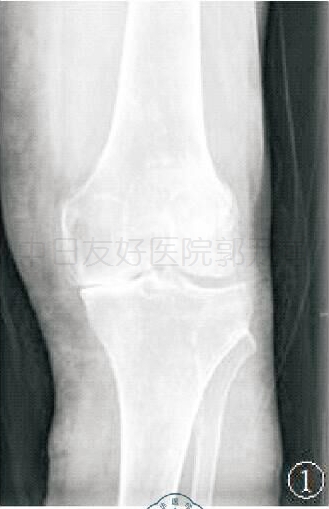

X线片一:术前前后位

标准的负重前后位 X 线可判断内侧间室关节软骨的磨损,若内侧间室关节间隙变窄,股骨内侧髁与内侧胫骨平台呈“骨对骨”接触状态,符合单髁手术适应证。